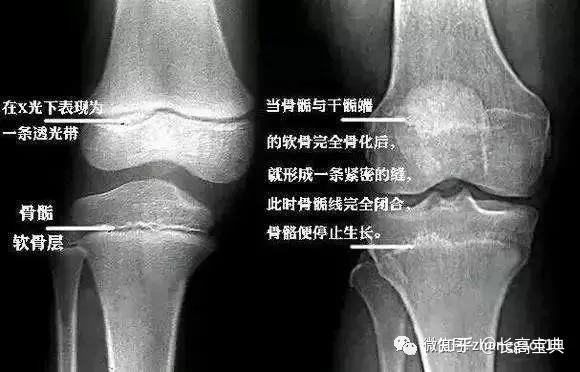

大腿和小腿中呈长管状的骨头叫长骨,长骨两端膨大部分就叫骨骺,决定你能否再长高。人的身高构成中,下肢长骨生长情况占主导地位:骨骺上的软骨细胞不断生长,使得长骨不断长长,进而人体长高。

有部分人的骨骺二十几岁才完全闭合,就有希望再冲刺一把身高。

当骨骺完全骨化闭合,你的长高进度条就达到100%了。

到医院拍 X 片确认一下你的骨骺是否完全闭合了:闭合前的骺板是一条透亮的区带,闭合后透亮区就消失了。